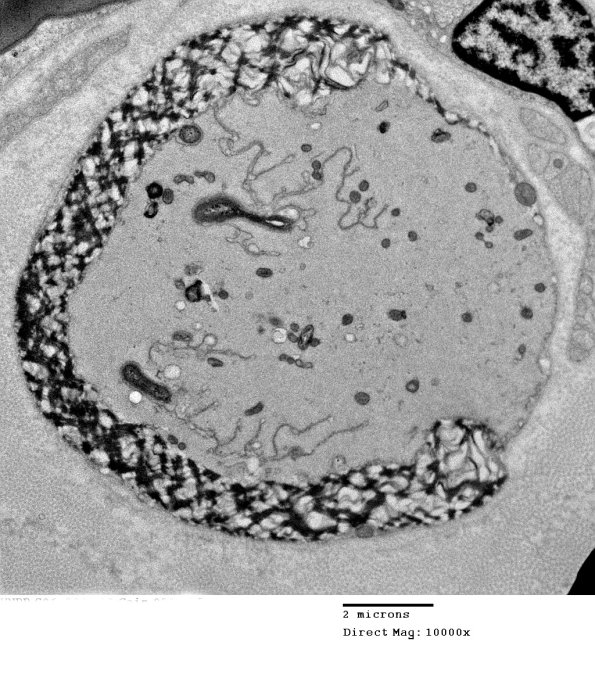

16E1,2 This shows several different patterns of myelinopathy as well as intra-axonal processes. (electron micrographs)